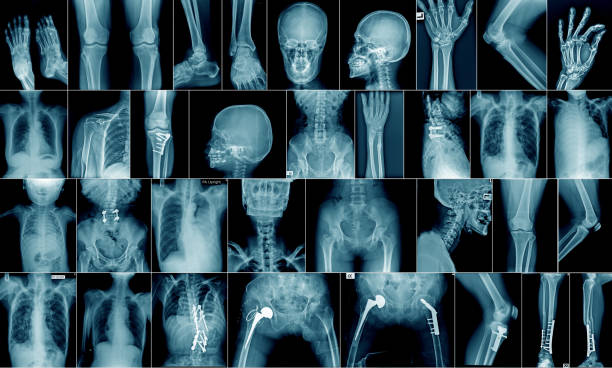

Los rayos X son un tipo de radiación

llamada ondas electromagnéticas. Las imágenes de rayos X muestran el interior

de su cuerpo en diferentes tonos de blanco y negro. Esto es debido a que

diferentes tejidos absorben diferentes cantidades de radiación. El calcio en

los huesos absorbe la mayoría de los rayos X, por lo que los huesos se ven

blancos. La grasa y otros tejidos blandos absorben menos, y se ven de color

gris. El aire absorbe la menor cantidad, por lo que los pulmones se ven negros.

El uso más común de los rayos X es para

ver huesos rotos, pero los rayos X se utilizan también para otros usos. Por

ejemplo, las radiografías de tórax pueden detectar neumonía. Las mamografías

utilizan rayos X para detectar el cáncer de mama.

Cuando a usted le sacan una

radiografía, es posible que deba usar un delantal de plomo para proteger

algunas partes de su cuerpo. La cantidad de radiación que recibe de una

radiografía es pequeña. Por ejemplo, una radiografía de tórax expone a una

dosis de radiación similar a la cantidad que está naturalmente expuesto del

ambiente por un periodo de 10 días.